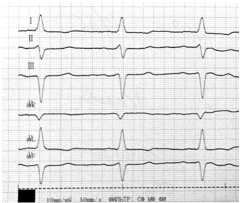

В течение последующих 4 лет записей в амбулаторной карте нет. В 2012 году обратилась в поликлинику с жалобами на дискомфорт в области сердца. Пациентка направлена к кардиологу. Снята ЭКГ и с диагнозом: ИБС: острый инфаркт миокарда (неизвестной давности) пациентка госпитализирована по «скорой помощи» в кардиореанимационное отделение многопрофильного стационара (рис. 1).

Рисунок 1. ЭКГ больного (59 лет)

Таким образом, неадекватный контроль гликемии, применение в течение длительного времени неэффективной схемы сахароснижающей терапии, отсутствие консультации с эндокринологом и зав. отделением (многократные визиты в поликлинику и без результатов), потеря контакта с больной почти на 4 года привели к тому, что развилось одно из грозных осложнений СД – острый инфаркт миокарда.